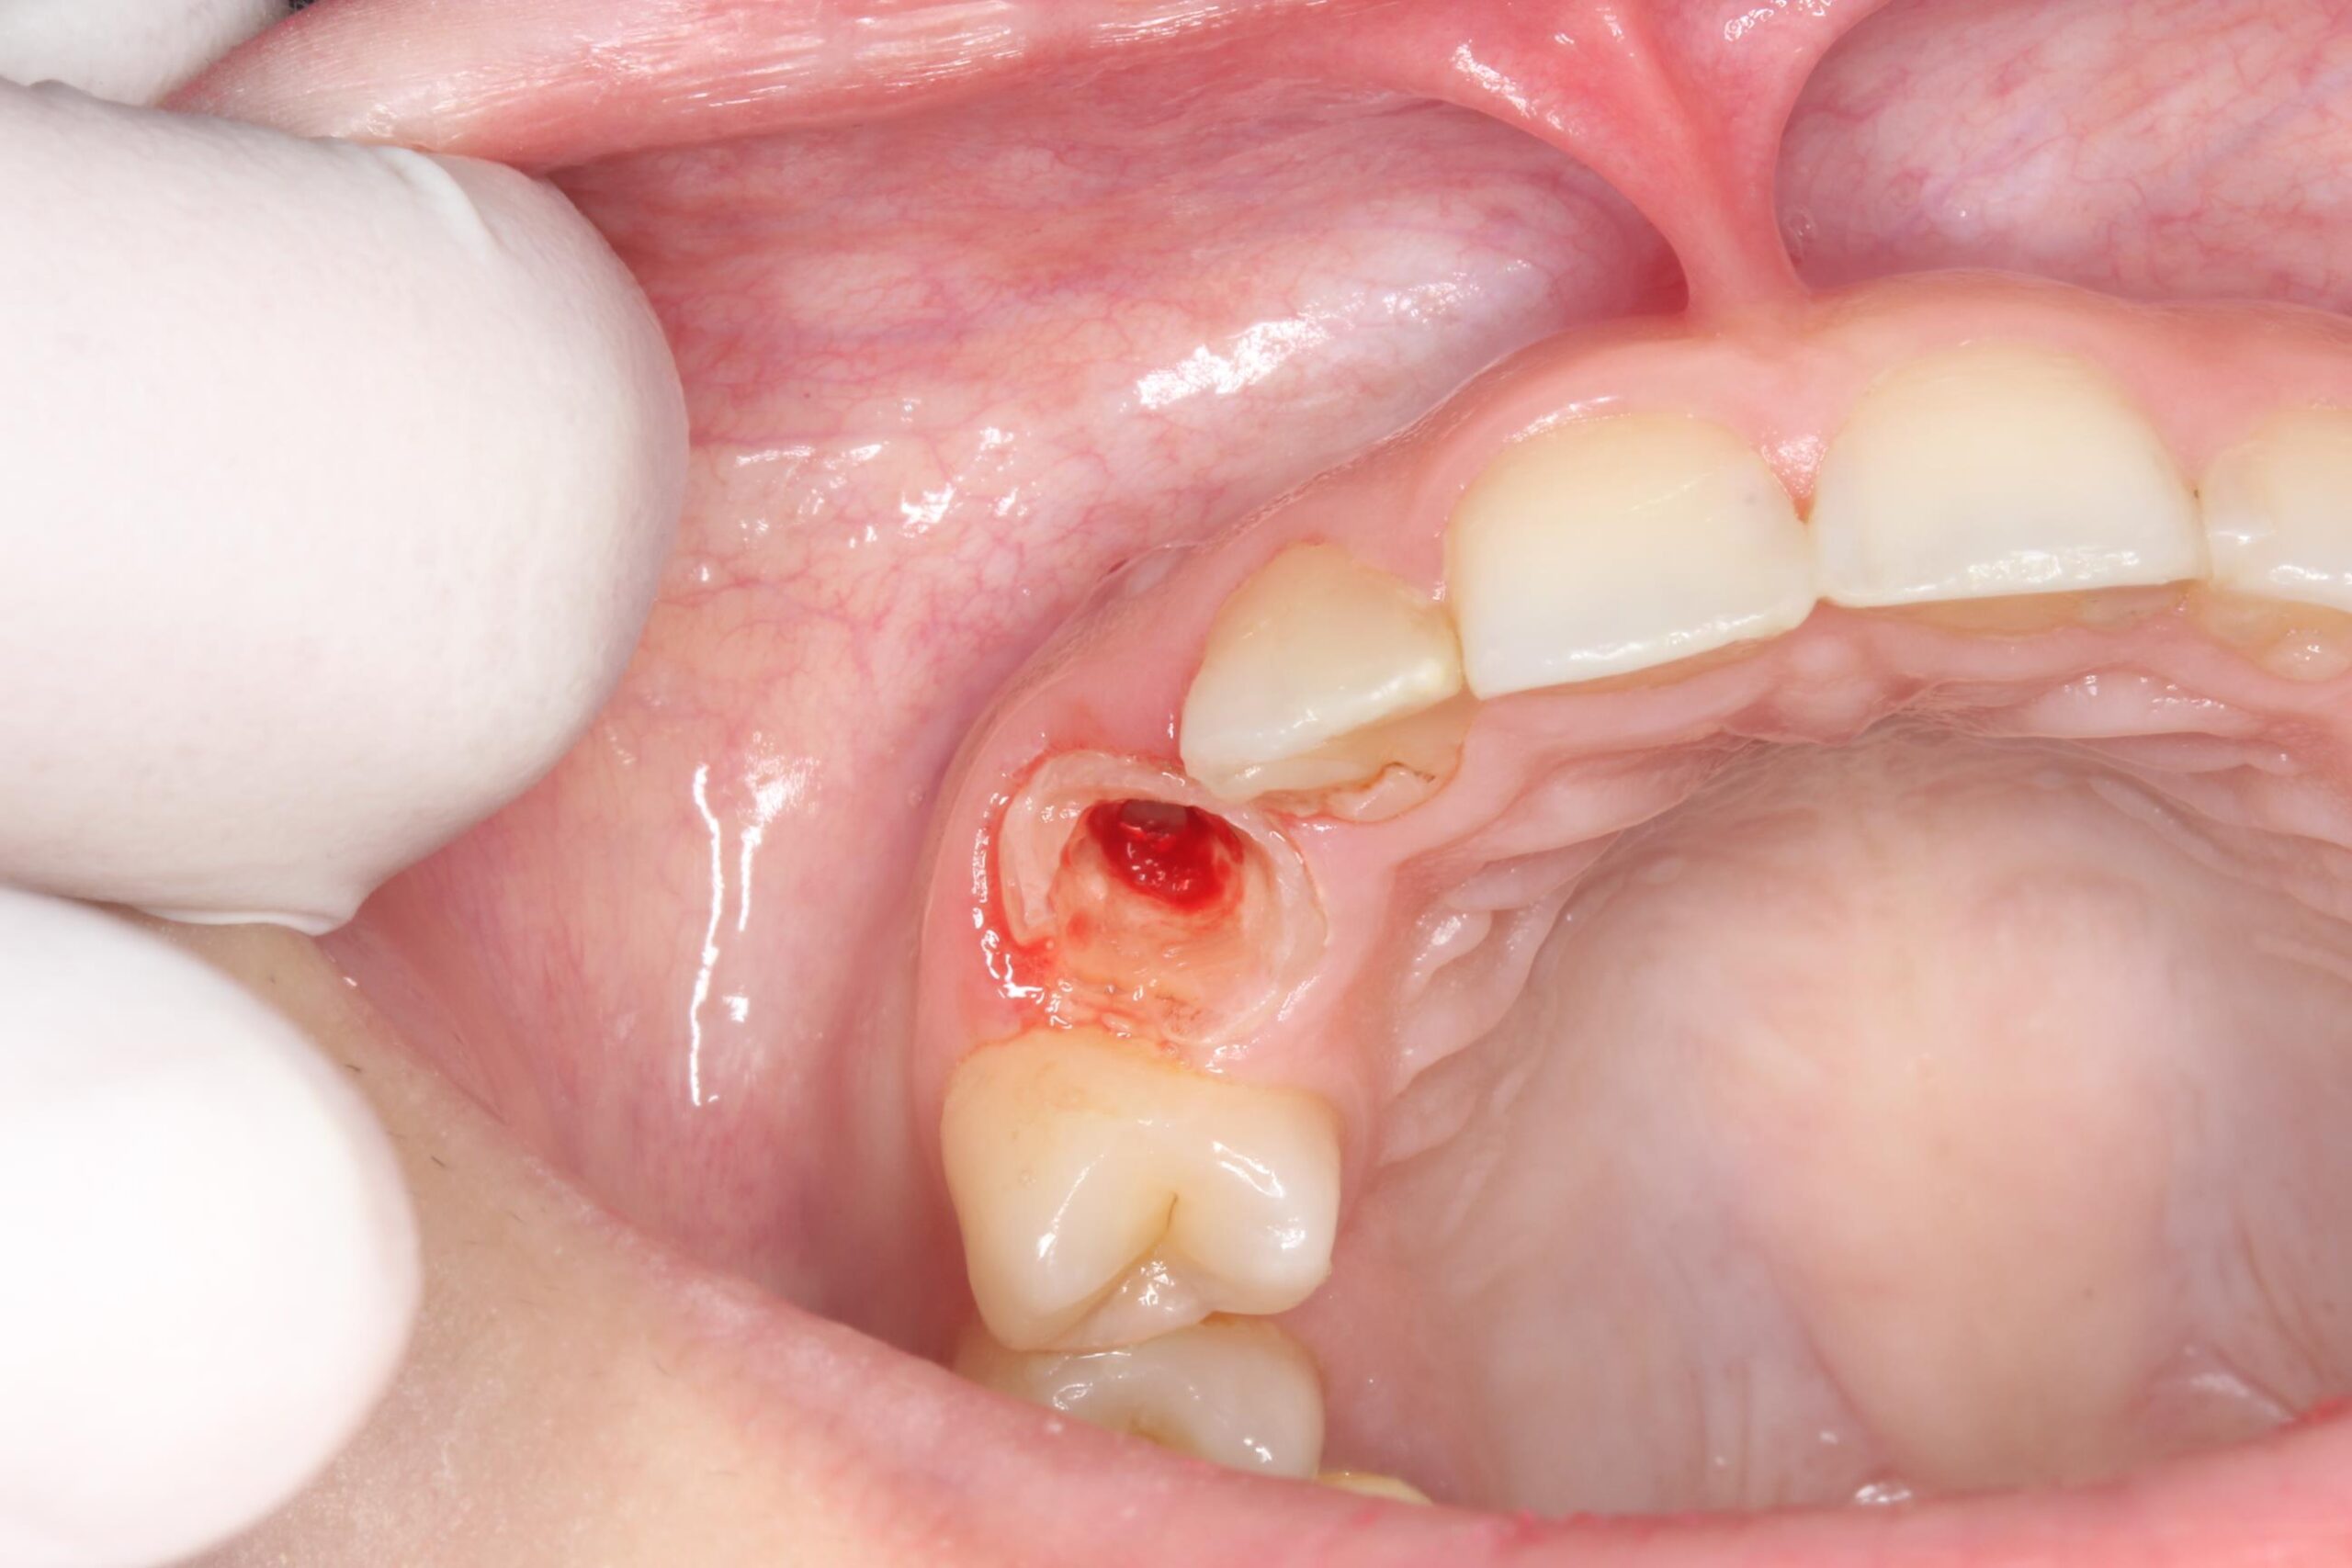

症例09

60代 男性 折れている歯を眠っている間に完全無痛でインプラントをして欲しい

歯根破折の確定診断

| 主訴 | 折れている歯を眠っている間に完全無痛でインプラントをして欲しい。インプラント手術自体をいかに痛みや不安がなく治療ができる医院がないかを探していた。抜歯と同日のインプラント手術を「完璧にできる」という歯科医師に治療してもらいたいと思っている。 |

|---|---|

| 年代・性別 | 60代 男性 |

| 治療部位 | 左下7 |

| 治療費用 | インプラント手術料 300,000円 |

| 手術回数 | 2回 |

| 治療期間 | 4ヶ月 |

| 手術時間 | 90分 |

| 治療回数 | 5回 |